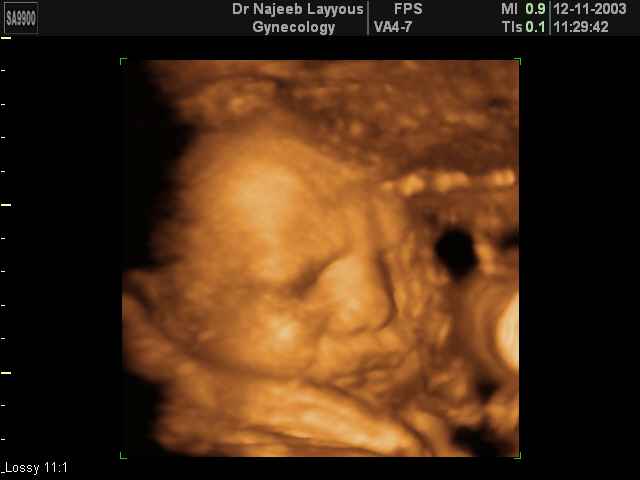

3D Fetal Face Ultrasound Scan Photos